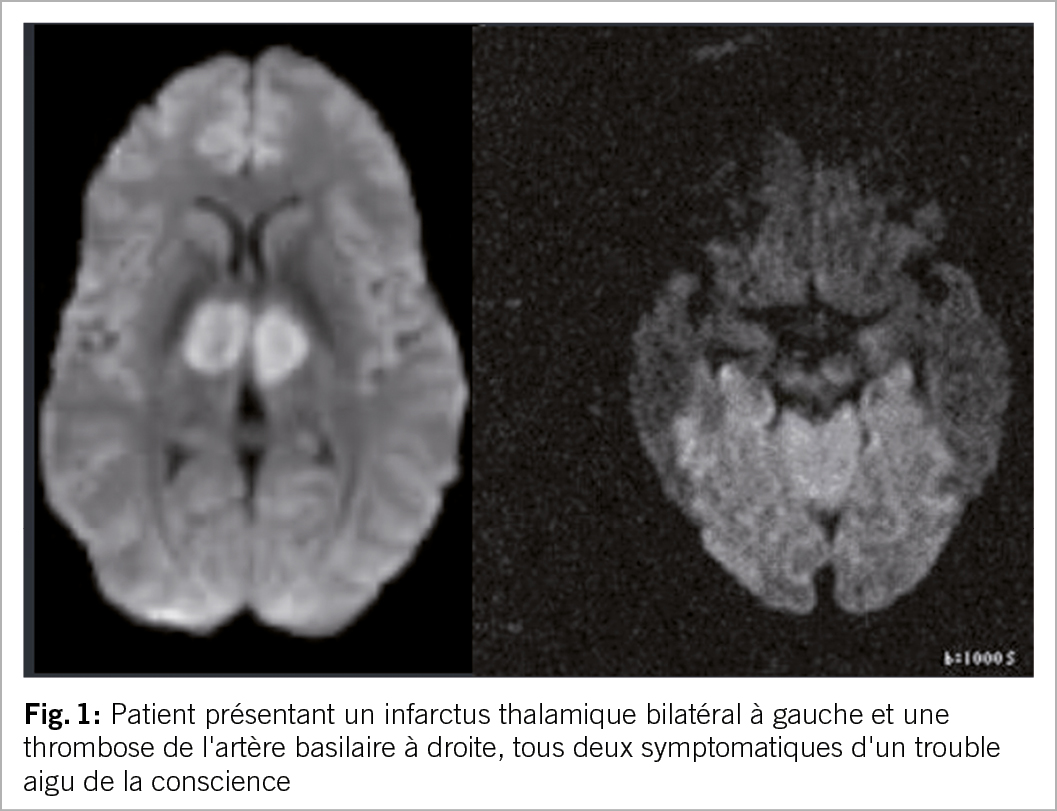

Le syndrome « top of the basilar » est causé par une occlusion de la partie distale de l’ artère basilaire ; les patients peuvent se présenter avec une perte de conscience et une tétraplégie (11). Les modifications pupillaires et les signes oculomoteurs fournissent des indices, mais un scanner ou une angiographie par résonance magnétique sont généralement nécessaires pour confirmer le diagnostic (11). Des troubles de la conscience peuvent également survenir en cas d’ infarctus thalamique bilatéral, généralement en association avec une paralysie du regard vertical (12). Les situations insidieuses sont celles où le patient est victime d’ un AVC peropératoire touchant la circulation postérieure et présente des troubles de la conscience persistants post-opératoires, attribués à l’ anesthésie (fig. 1).